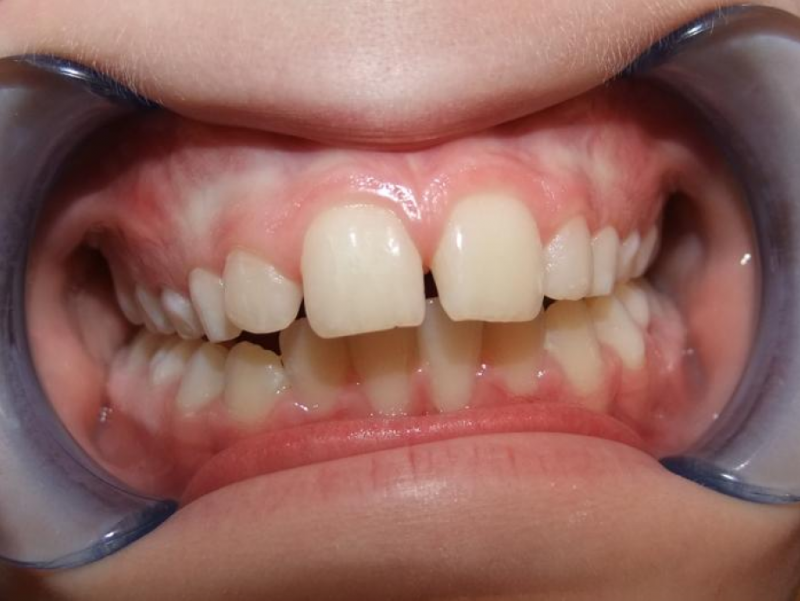

Leeftijd bij aanvang: 9 jaar

1-6 Bonded Hyrax + volledig vast onderkaak & TransForce

7-13 Twin Block